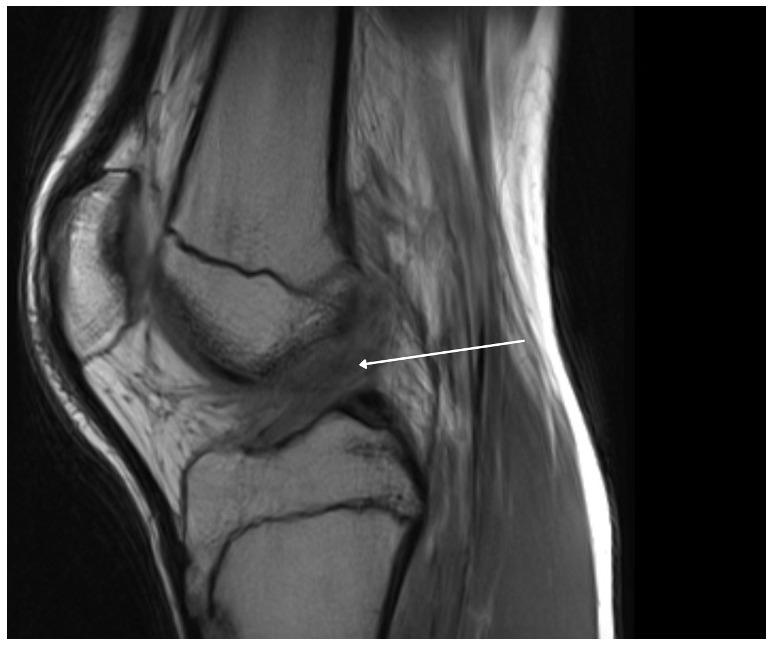

A 15-year-old male weighing 150 pounds and standing 6 ft 1 in tall, with no past medical history, presented to the clinic with buckling, catching and locking of the medial knee. He is a high school athlete who sustained a non-contact injury involving knee flexion combined with external rotation during a football game. He immediately reported a pop in the knee followed by stiffness and swelling. Clinical examination revealed joint effusion and medial and lateral joint line tenderness, on the inferior pole of the patella and tibial tubercle. Passive range of motion was limited, and both Lachman and McMurray tests were positive. Radiographs confirmed open physes with no evidence of fracture or malalignment., MRI demonstrated bony contusions and a substantial ligament injury, with a high-grade partial ACL tear, along with questions of peripheral posterior medial meniscus root tearing (Figures 1, 2). Management options were discussed with the patient, and he elected to proceed with surgical fixation. An additional consent was obtained from parental guidance for the possible publication of the surgical technique.